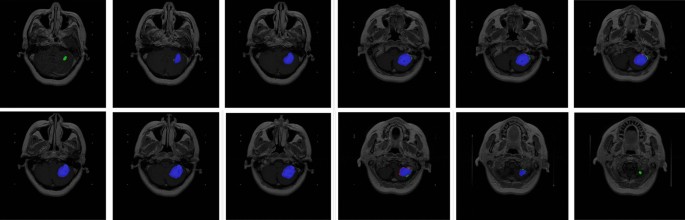

Figure 6 visualize the segmentation results. The left-hand side was the original MRI image and the right-hand side shown the ground truth where the tumors was in the slice. The middle is the segmentation, the blue part was the true positive, the green region was the false negative and the area in red was false positive. More segmentation result shown in Figure 7.

Visualization the segmentation by the ensemble strategy.